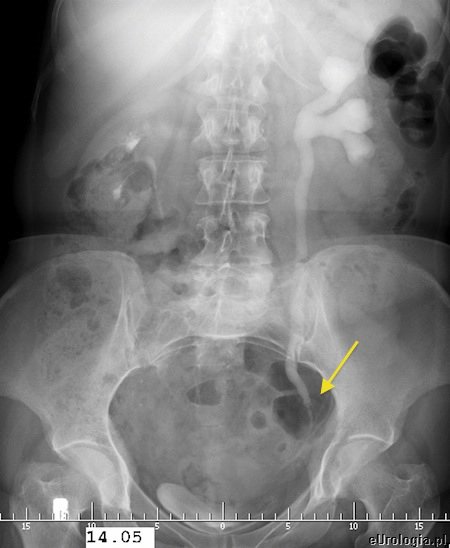

Kamica moczowodowa czyli potocznie kamień w moczowodzie jest najczęstszą przyczyną kolki nerkowej. Złogi - kamienie z nerki mogą przemieścić się do moczowodu blokując odpływ moczu z nerki. Zastój moczu w układzie kielichowo - miedniczkowym powoduje napięcie torebki nerkowej i wystąpienie ataku kolki. W zależności od lokalizacji kamień w moczowodzie może być uwidoczniony róznymi sposobami. Kamienie w górnym odcinku moczowodu i w okolicy ujścia pęcherzowego moczowodu czasami możliwe są do uwidocznienia w USG. Większość kamieni w moczowodzie widoczna jest na zdjęciu przeglądowym jamy brzusznej. W celu uwidocznienia miejsca przeszkody w odpływie moczu z nerki wykonywane jest badanie urograficzne. Urografia jest badaniem obrazowym pozwalającym na ocenę czynnościową i anatomiczną układu moczowego.

Fot. Urografia - widoczne poszerzenie UKM lewej nerki i lewego moczowodu do wysokości złogu.